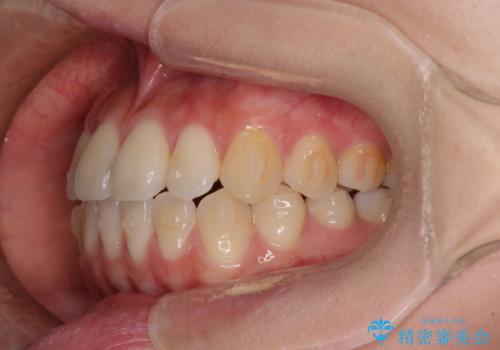

- 前歯のクロスバイトが気になり、インビザラインによる矯正治療を希望して来院された患者様です。

上顎側切歯(上の真ん中から2番目の歯)が舌側転位している場合、インビザラインでは仕上げきれないことが多く、更には無理して動かそうとすると歯髄壊死を起こすリスクが高いと言われています。

インビザラインで歯列を移動する前に、上顎前歯をワイヤー矯正で整え、その後上下歯列をインビザラインにて矯正治療を行うこととしました。

舌側転位している側切歯特有の、切縁の位置が不揃いであったり、根元が内側に引っ込んだ状態であったりという、インビザライン独特の仕上がりになることなく、きれいに整った歯列とすることができました。